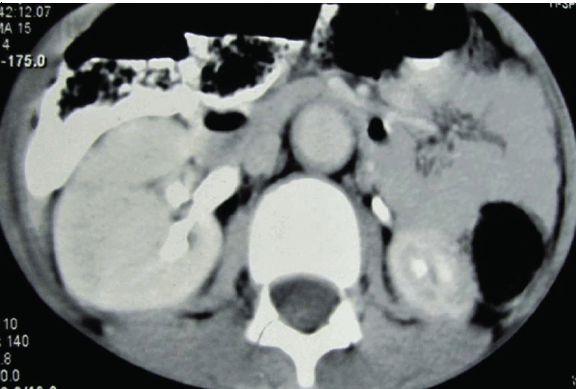

A 13-year-old boy was admitted with persistent headache and vomiting for one month and repeated generalized tonic clonic seizures for two days. He had no history of fever, chest pain, palpitations, claudication or visual disturbance. Enquiry about joint pain, photosensitivity, oral ulcers and recurrent infections were not contributory. His past history was unremarkable and his parents had no reason to worry about his milestones. The boy had good scholastic performance and had no difficulty in outdoor games. There was no history of contact with tuberculosis. Clinical assessment revealed an alert, conscious and co-operative boy, with corroborative apparent and chronological ages. Clinical examination of the patient showed blood pressure was 240/150 mmHg in both the upper limbs, and all peripheral pulses were palpable. Blood pressure was similar in upper and lower limbs and no radio radial or radio femoral delay was appreciated. Edema was absent and neck veins were not engorged. Systemic examination was unrewarding except for a systolic bruit heard over the epigastrium, which extended along the midline up to 1 cm above the umbilicus. Ophthalmoscopy was normal as well. Counts, baseline biochemistry (sugar, urea, creatinine, LFT, lipid profile, Na, K, TSH and FT4) and ECG were all within normal limits. X-ray of chest suggested borderline left ventricular hypertrophy and echocardiography with Doppler demonstrated eccentric hypertrophy of the left ventricle (left ventricular internal diameter 4.35 cm, LVIDs 2.98 cm, LVEF 60%). Moreover, a localized narrowing of a suprarenal segment of the abdominal aorta with a systolic pressure gradient around 40 mmHg, systolic pressure gradient 100 mmHg in celiac axis and superior mesenteric arteries. (Figure 1) Ultrasonography (USG) of abdomen with Color Doppler was done. Kidney sizes were 10.6 cm (right) and 8.5 cm (left) in the long axes. The right renal artery and interlobar arteries demonstrated normal spectral waveforms but the left renal artery could not be imaged properly. An abrupt focal dilatation of the abdominal aorta 1.7 cm (approx.) below the origin of superior mesenteric artery was observed. The dilated segment spanned 6.27 cm in the craniocaudal direction and measured 1.6 cm in diameter. A focal narrowing just before the dilatation was noted on USG. (Figure 2) In view of the seizures prior to admission, contrast enhanced computed tomography (CT) of brain was performed and bilateral symmetrical non-enhancing hypodense lesions involving the parieto-occipital areas suggestive of infarcts were noted. But repeat CT scan was normal and suggesting the diagnosis of reversible posterior leukoencephalopathy rather than infarct. Contrast enhanced computed tomography (CECT) abdomen corroborated the findings on USG and showed relatively small left kidney with poor enhancement patterns, suggestive of left renal artery stenosis. A focal dilatation of the abdominal aorta was also noticed on the CT scan. Tests for ANF (HEp2 method), RA factor and cANCA were all unrewarding. Magnetic resonance angiography of the aorta and its branches were performed. This showed a normally located aortic arch and the ascending aorta was seen to arise from the left ventricle with no evidence of any abnormal dilatation or flap. The arch of aorta and thoracic aorta were also normal. A distinct fusiform dilatation of abdominal aorta was seen just below the origin of the superior mesenteric artery. This dilated segment had a diameter of 19 mm and the craniocaudal extension of the dilated segment was about 63 mm. Focal narrowing of abdominal aorta as well as left renal artery was noted just proximal to the dilatation. The dilated segment extended below up to the division of aorta into the iliac vessels. (Figure 3) The boy was referred for vascular surgery but the patient refused any operative procedure. He was put on metoprolol (50 mg) twice daily and amlodipine (10 mg) daily and has been on irregular follow-up for the last 14 months, his last blood pressure record was 160/90 mmHg.

Cursor on image to zoom/Click text to open image

Figure 2: Contrast enhanced computed tomography of abdomen showing small left kidney and focal dilatation of the abdominal aorta.